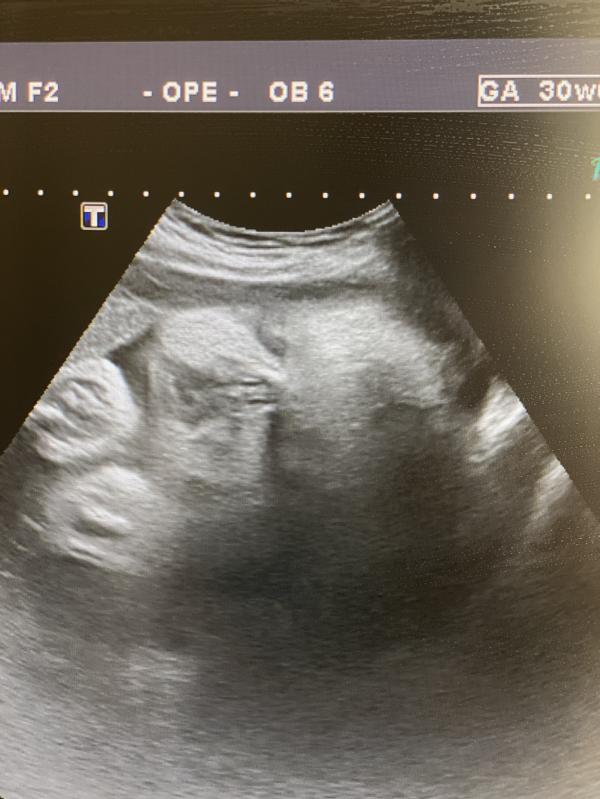

На узи узнала что 22 неделя беременности, девочки сказать что у меня был шок - не сказать ничего. У меня была истерика…

Я реально 22 недели абсолютно не чувствовала ничего. Живота не было.

Сколько плод весит по узи? Если живота нет, плод отстаёт в развитии, так врачи говорят.